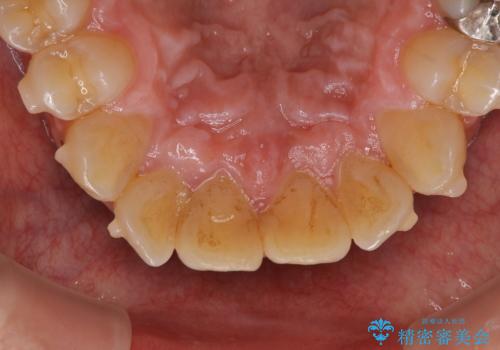

- インビザラインの治療中ですが、歯石やステインが気になるとのことでした。

コーヒーが大好きでよく飲むそうです。

全体的に歯石やステインが付着していたため、エアフロー60分コースを行いました。